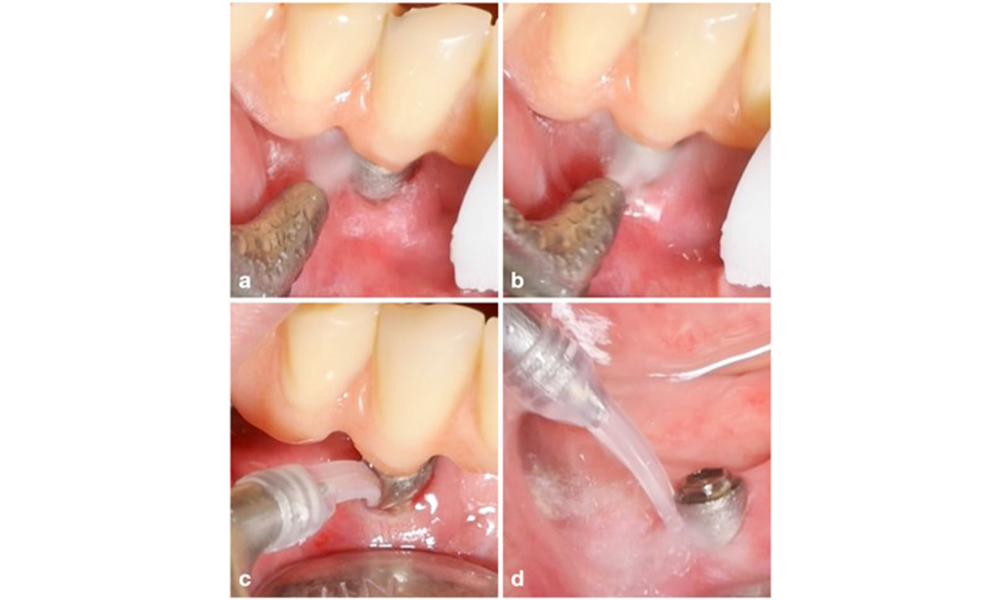

The choice of equipment depends on clinical circumstances, such as the distinction between calculus and soft plaque. Thus, in cases with calculus, titanium or plastic curettes, or specially designed tips for ultrasonic scalers should be used first, followed by the use of an air-polishing device (figure 7). In cases with only soft plaque accumulation, an air-polishing device alone can be sufficient. Air-polishing devices are operator and patient friendly and at least as efficient as standard instruments (Schwarz et al. 2015a).

Patient case with peri-implant mucositis, poor oral hygiene and calculus accumulation (a). In such case the combination of different equipment is advisable, i.e., specially designed tips for ultrasonic scalers are necessary to remove the calculus (b), and an air-polishing device helps in removing remaining soft biofilm (c–d).

Management of peri-implantitis at implants judged as treatable consists of a non-surgical phase, which is often followed by surgical intervention. For the non-surgical approach, similar measures as those applied for the treatment of peri-implant mucositis are used; based on laboratory experiments air-polishing devices with a subgingival nozzle appear to provide certain advantages in terms of biofilm removal, compared to hand- or ultrasonic instruments (Herrera et al. 2023; Moharrami et al. 2019; Ronay et al. 2017) (figure 9).

Patient case with peri-implantitis. The non-surgical treatment is performed by using the supragingival (a-b) and subgingival handpiece of an air-polishing device (c-d). Removing the supra-construction provides better access to the implant surface (d).

Figure 9. Patient case with peri-implantitis. The non-surgical treatment is performed by using the supragingival (a-b) and subgingival handpiece of an air-polishing device (c-d). Removing the supra-construction provides better access to the implant surface (d).